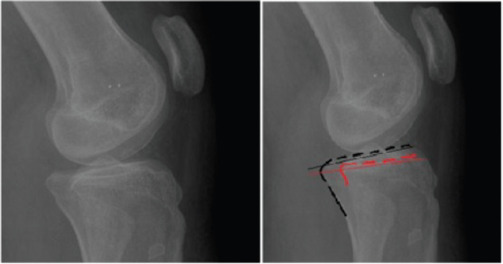

Methods: In this retrospective study, children who underwent guided growth by the eight-plate for genu varum or valgum were included. Thirty-eight extremities of 23 children (14 girls and 9 boys; mean age = 9.2 years, age range = 3-17 years) were then divided into two groups according to the plate location in the sagittal plane (anterior or midline). Preoperative and postoperative TS were measured from the medial and lateral tibial plateaus separately.

Results: The mean follow-up was 34.3 (range = 12-96) months. The mean preoperative and postoperative medial TS were 4.05 ± 5.65 and 0.83 ± 3.91 degrees, respectively, in 18 patients in whom anterior epiphyseal plates were placed (P = 0.004). The mean preoperative and postoperative lateral TS were 4.88 ± 5.33 and 0.11 ± 3.34 degrees, respectively, in 18 patients in whom anterior epiphyseal plates were placed (P < 0.001). The mean preoperative and postoperative medial TS were 4.2 ± 5.19 and 4.9 ± 6.02 degrees, respectively, in 20 patients in whom midline epiphyseal plates were placed (P = 0.532). The mean preoperative and postoperative lateral TS were 5 ± 5.51 and 4.8 ± 5.7 degrees, respectively, in 20 patients in whom midline epiphyseal plates were placed (P = 0.871). Postoperative TS was decreased in anteriorly located eight-plates, and medial and lateral plateau measurement was significant (P = 0.004 and P < 0.001, respectively). Postoperative TS changes in midline-placed eight-plates were not significant regarding the medial and lateral plateaus (P = 0.532 and P = 0.871, respectively).

Conclusion: The results of this study have shown that TS decreases following guided growth by the eight-plate in children in whom plates are placed at the anterior epiphysis. To prevent TS changes, the eight-plate should be placed in the midline position at the sagittal plane.